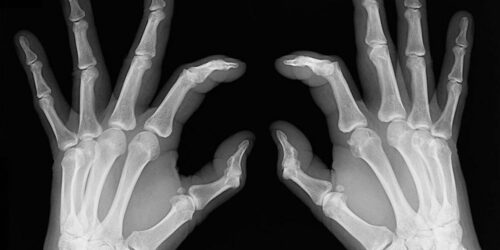

Early signs of rheumatoid arthritis and how to catch them

Rheumatoid arthritis causes chronic inflammation of joints, which results in joint pains, inflammation and bone deformation. It usually starts slowly with pain in some parts of the body that can come and go in the beginning and then spread within weeks or months. It is better in this day and age to always be aware of your health problems and not to ignore slightest of joint pains.